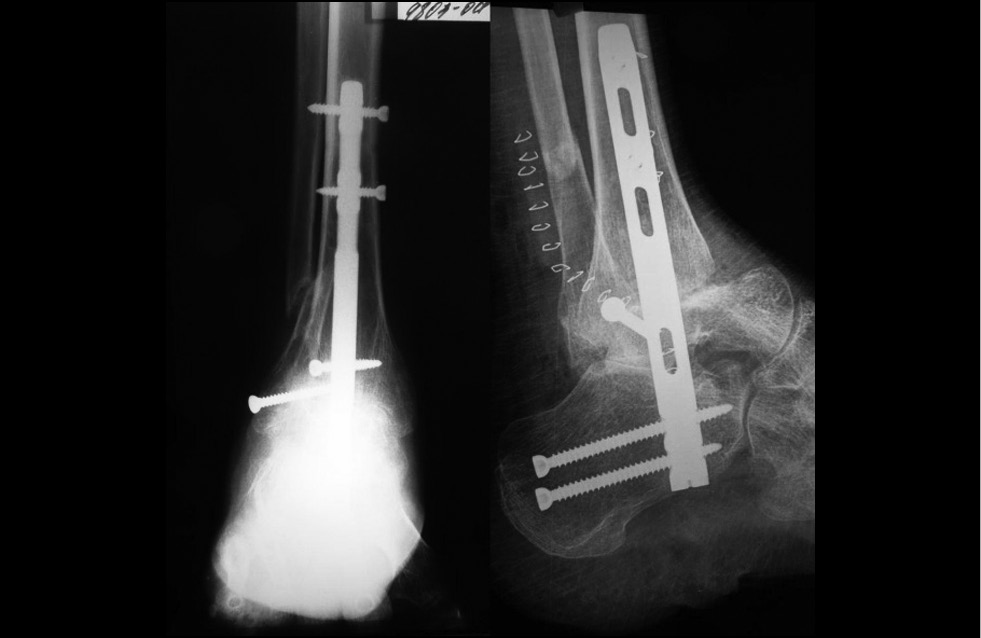

Другая нога была оперирована через 1 год (рис. 6), более года пациент передвигается самостоятельно с опорой на обе ноги (рис. 7). Кроме того, он выполнял подобранный комплекс физических упражнений, который на фоне медикаментозной терапии позволил почти избавиться от судорожного синдрома, что существенно улучшило его самообслуживание и социализацию.1,2 Благодаря успешно проведенным операциям и правильно подобранному медикаментозному лечению и лечебной физкультуре, были значительно расширены возможности самообслуживания и социализации пациента. При повторном освидетельствовании пациент был переведен с I группы инвалидности на III группу, а также с момента начала лечения и по сегодняшний день отсутствует отрицательная динамика заболевания, чему свидетельствует шкала оценки интенсивности боли. При поступлении под наше наблюдение и лечение оценка по шкале была 7–8 баллов, в процессе лечения она снизилась до 0 баллов, вдвое улучшился показатель ЭНМГ, придя практически к норме.

Рис. 6. Послеоперационная рентгенограмма левой стопы и голеностопного сустава. Результат аналогичен предыдущему вмешательству

Fig. 6. Postoperative radiography of the left foot and ankle. The result is similar to the previous intervention